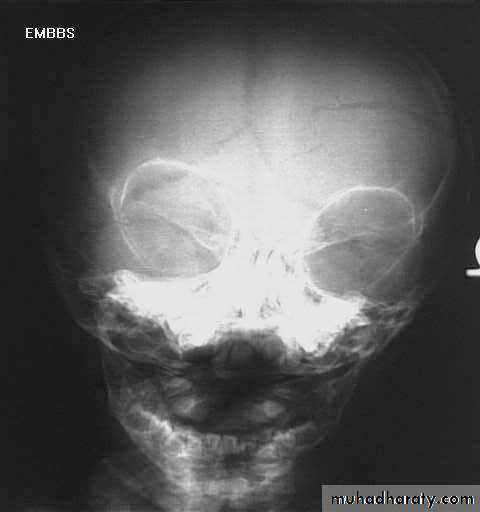

a. Plain skull x-ray

1. Can demonstrate the site and type of a skull fracture.

2. A foreign body can also be seen.

Skull Fracture

Nuro